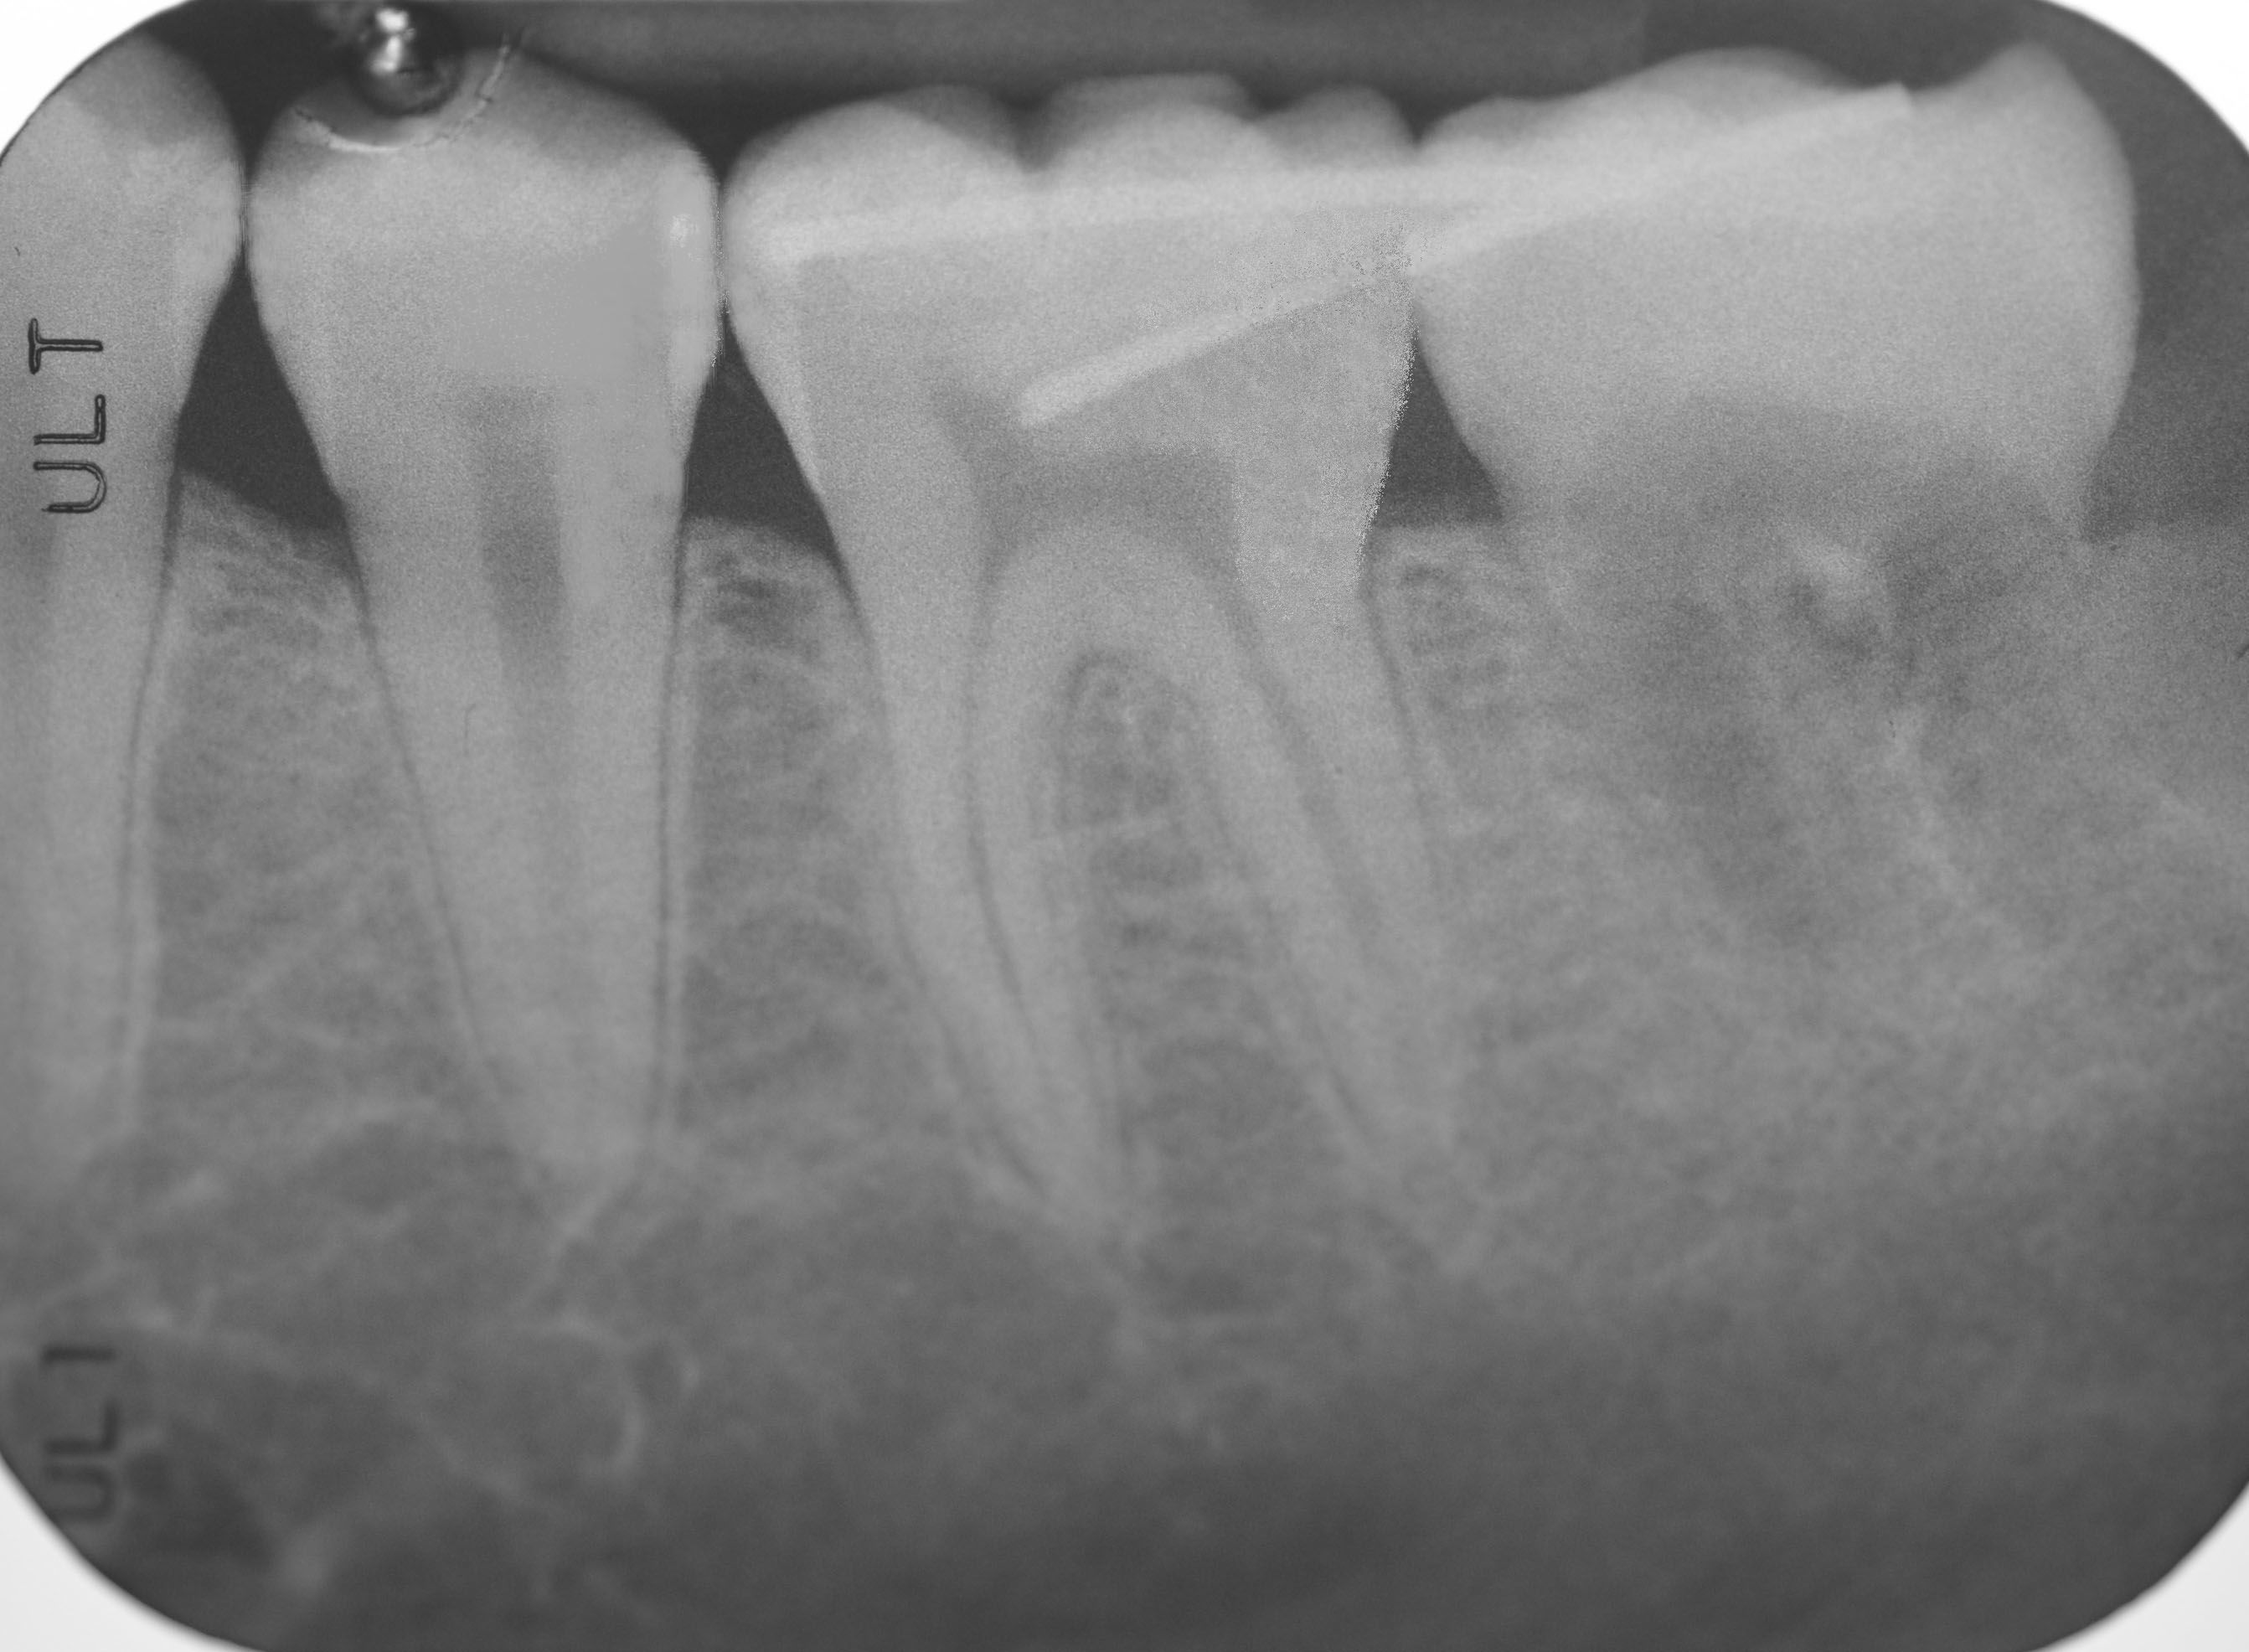

Viene eseguita una radiografia panoramica che mostra la non recuperabilità di un molare inferiore a causa della presenza di una carie di grandi dimensioni.

Il dente trapiantato a 5 anni di distanza appare stabile e perfettamente integrato coi tessuti limitrofi.